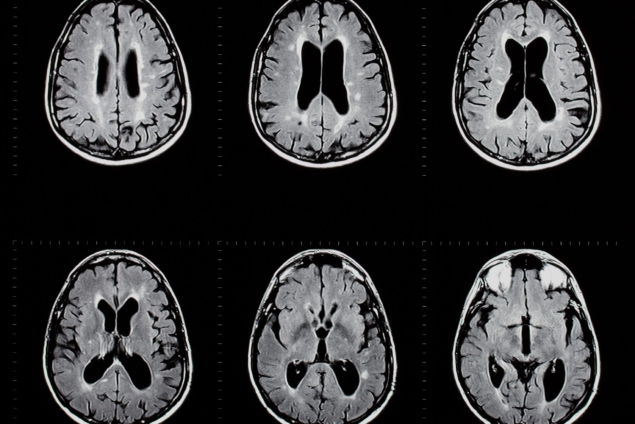

MS is a chronic, immune-mediated disease of the central nervous system that leads to neurological symptoms and disability, affecting one out of every 3000 people in the world.

While it’s the most common non-traumatic cause of neurological disability in young adults, it’s a disease that is often misunderstood by both patients and providers, largely because the symptoms often mimic other conditions. MS symptoms can slowly appear or creep up on you suddenly.